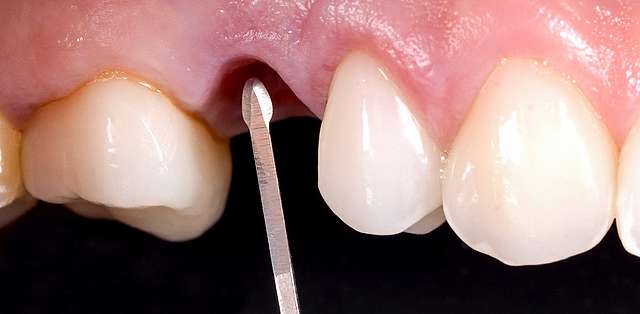

The mock-up just like a treatment plan can simulate a diverse array of procedures that vary on cases basis. In this case, we have dental implants and tissue grafts in posterior areas, on both sides, and ceramic veneers and crown lengthening in anterior side to balance the smile. As a fine detail , you can see how the dentist uses a black marker to simulate the area of the tooth which will be reduced. The mock-up, once accepted becomes a cental pillar in an interdisciplinary treatment. It will be used to determine how the gums will be remodelled , where the implants should be placed, and how the teeth need to be prepped for the future restorations.